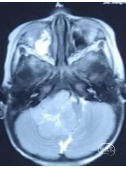

术前头部MRI

右侧桥小脑角区可见一不规则等T1、等-T2信号灶,大小约46*51*55mm3边界欠清,病灶突入四脑室内,第四脑室受压变窄,强化明显。